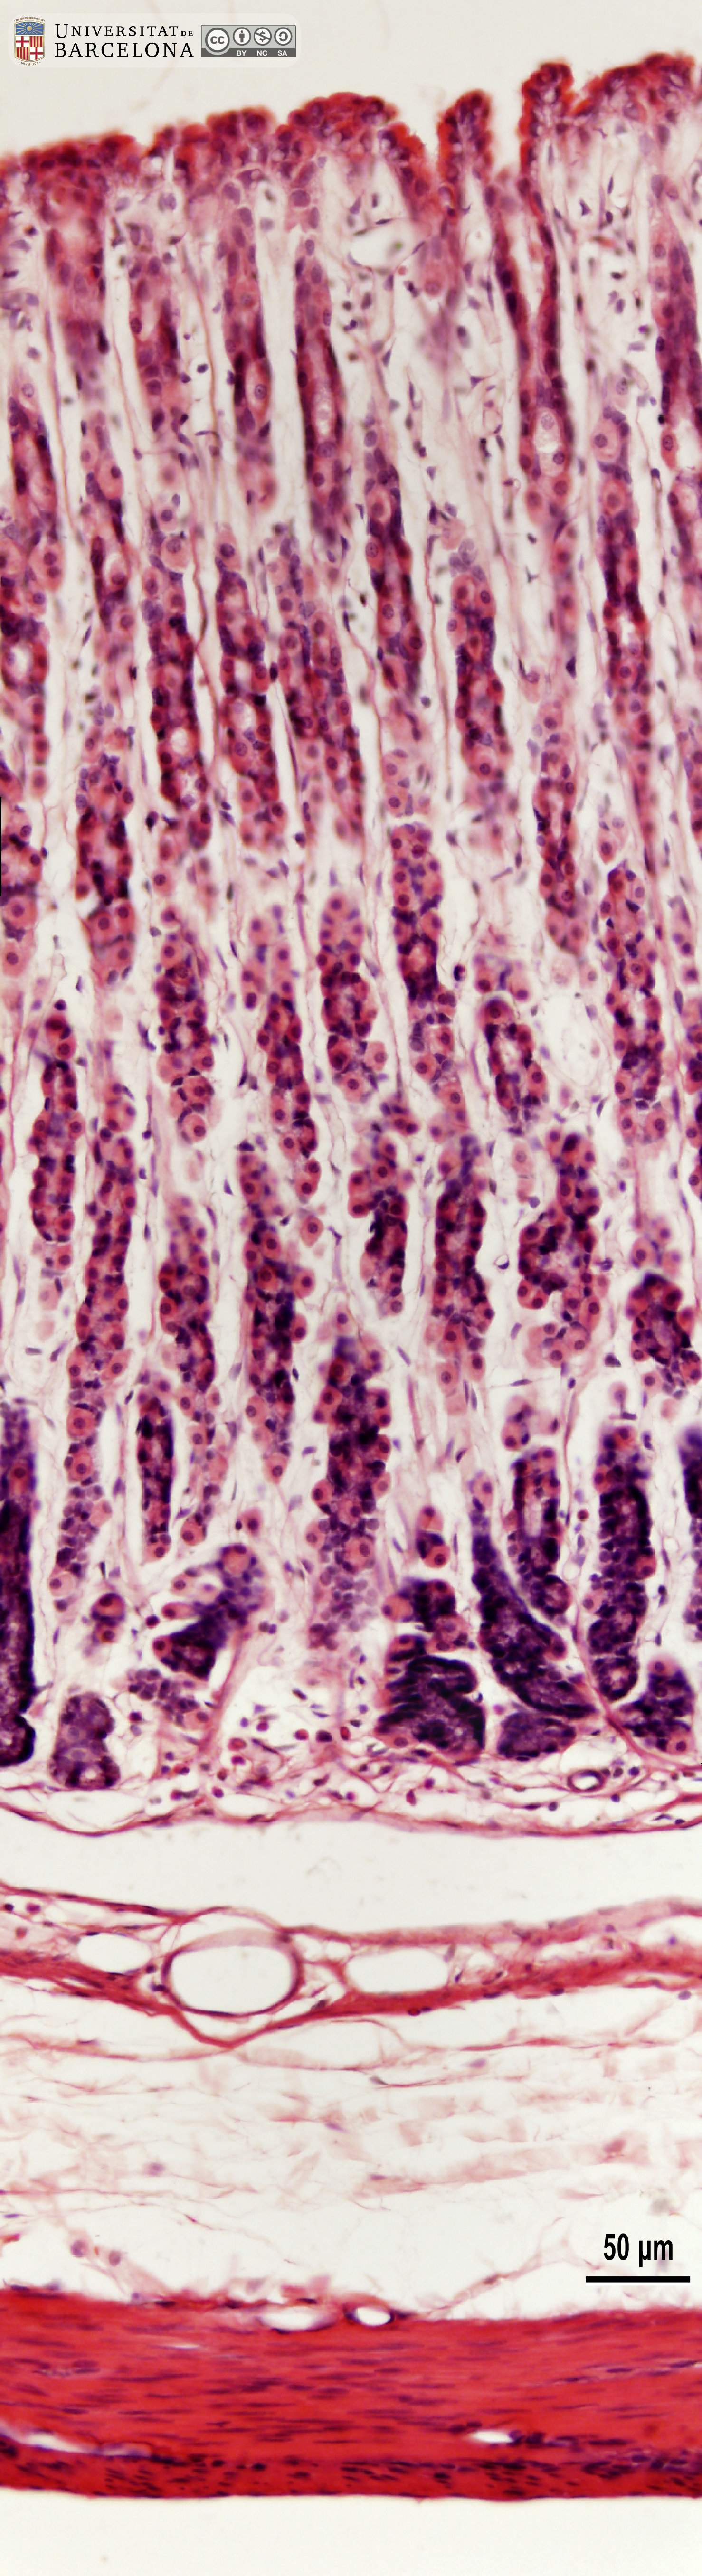

[ENG] A collection of micrographs illustrating the organisation of the stomach in rats. The layers of the gastric wall and their components –such as blood vessels, fibres and cell types– are shown in paraffin sections stained with hæmatoxylin-eosin stain or van Gieson trichrome. Semithin sections 2 µm thick were stained with toluidine blue. This collection complements the micrographs published by Dr Elena Sagristà i Mateo https://hdl.handle.net/2445/60213 — See also: https://diposit.ub.edu/dspace/browse?type=author&value=Sagrist%C3%A0+i+Mateo%2C+Elena

[CAT] Col·lecció de micrografies de l'organització de l'estómac de la rata. Es mostren les capes de la paret estomacal i els seus components (vasos sanguinis, fibres, tipus cel·lulars, etc.) en talls de parafina tenyits amb hematoxilina-eosina o el tricròmic de van Gieson i talls semifins de resina epoxi tenyits amb blau de toluïdina. Aquesta col·lecció complementa les micrografies publicades per la Dra. Elena Sagristà i Mateo https://hdl.handle.net/2445/60213 — I també: https://diposit.ub.edu/dspace/browse?type=author&value=Sagrist%C3%A0+i+Mateo%2C+Elena